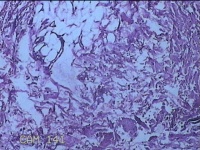

左侧腋下结节

性别

女

年龄

22岁

临床诊断

皮下结节;皮脂腺囊肿

一般病史

发现左侧腋下结节伴隐痛不适1周余。

标本名称

大体所见

灰白暗红色带皮肤样结节2.5x1.5x0.7cm一个,表面糜烂,切开结节呈实性,切面灰白淡黄色,质软。

图3